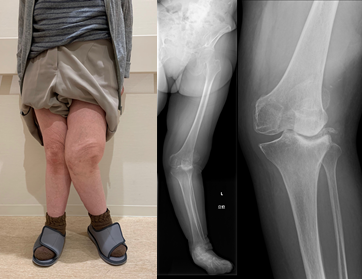

高位脛骨骨切り術 (high tibial osteotomy: HTO)

変形性膝関節症や大腿骨内顆骨壊死症などに適応があります。

脛骨の近位部を骨切りし、O脚に変形した下肢を軽度X脚に矯正し、荷重による負担を膝外側に移動することによって、膝内側の痛みを緩和する方法です。変形の程度によって開大式と閉鎖式骨切り術を使い分けております。

また、若年者で骨壊死を伴う症例には、骨軟骨片移植による関節内治療も併用し、良好な成績を得ています。